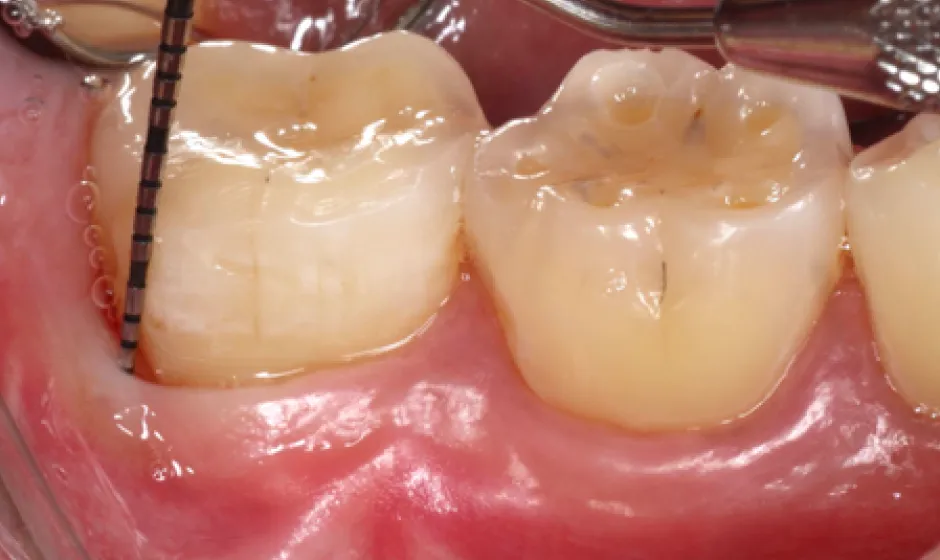

01精密根管治療

「抜くしかない」と言われた歯でも、根の中の感染を適切に抑えられる治療技術があれば、歯を残せる可能性があります。根管は非常に細く複雑で、わずかな取り残しが痛みや腫れの再発につながることもあるため、当院では必要に応じてCTやマイクロスコープを活用し、原因を見極めながら丁寧に処置を進めます。

医療法人大杉歯科医院が大切にしているのは、早く終える治療ではなく、歯を守る治療。津市で、できるだけ天然歯を残したい方の選択肢になれるよう取り組んでいます。症例1

- 治療名

- マイクロスコープとラバーダムを使用した精密根管治療

- 患者様

- 30代男性

- 執刀医

- Dr. 大杉

- 治療期間

- 3ヶ月

- 治療費

- 精密根管治療:130,000円(税込)

築造:40,000円(税込) - リスク

- 治療中〜治療後に痛みが出る場合あり

再感染・治癒不全の可能性

補綴後も定期管理が必要